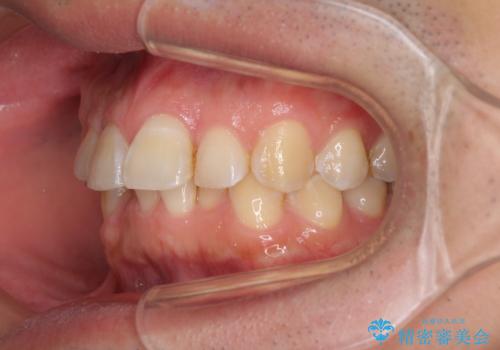

ディープバイトと叢生を解消 インビザライン矯正

- 前歯のデコボコを強い咬みしめを気にして来院された患者様です。

インビザラインを用いて、前歯の叢生を解消するとともに、ディープバイトを改善していくこととしました。

ディープバイトが改善されたことで、顎への負担が軽減され、更には上顎前歯の突出感も改善することができました。

矯正治療後には欠けてしまった修復物をセラミックインレーにて修復治療しました。